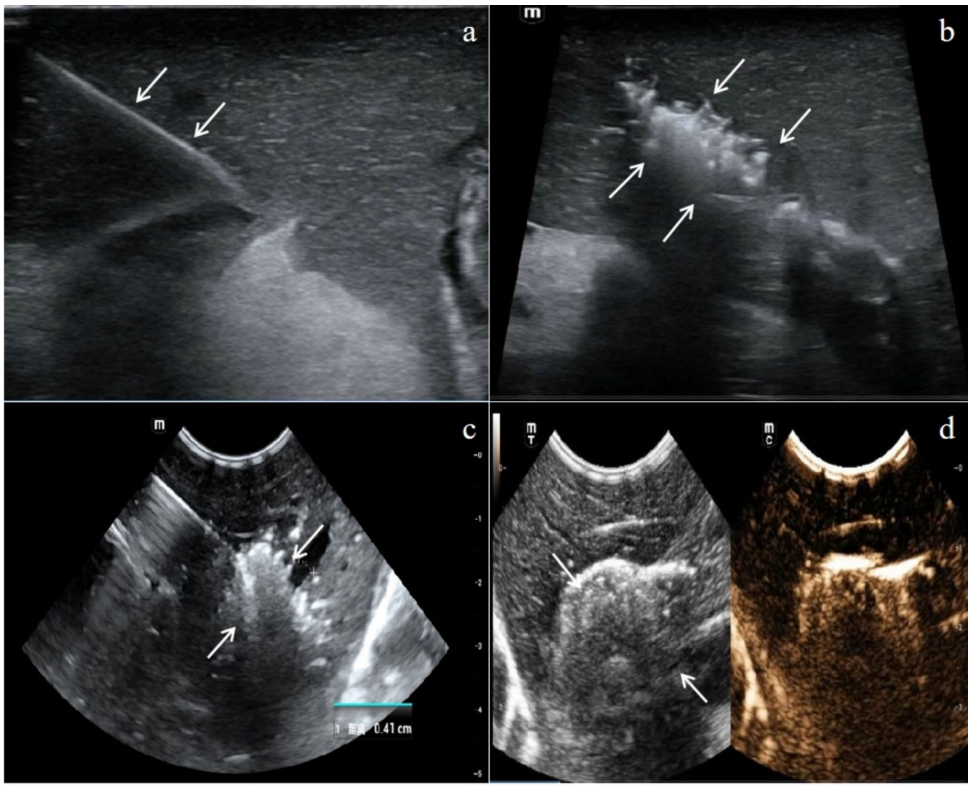

超声图像分析

Flash+MBs+MWA组止血灶回声增强且边界清晰,凝固范围显著大于其他组,证实微泡爆破产生的空化效应能扩大热凝固区域。